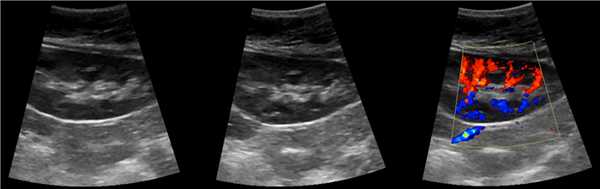

Трансплантированная почка обычно располагается вдоль поверхности подвздошнопоясничной мышцы, ее эхогенность совпадает с эхо- генностью обычной почки. Эхографические признаки отторжения трансплантата включают: патологическое увеличение размеров почки, гидронефроз, паранефральное скопление жидкости, гематомы, абсцессы и экстраренальные накопления мочи. При допплерографии почечного кровотока обычно определяется увеличение сосудистого сопротивления или полное прекращение кровотока в главной почечной артерии, междолевых артериях, дугообразных артериях (для исключения отторжения), почечной вене (для исключения перегиба почечной вены).

При снижении скорости кровотока и повышении индекса резистентности до 0,70 и более, как в первой, так и во второй группах, показатели УЭСВ составили от 28,00 до 39,45 кПа. Повышение жесткости паренхимы почечного трансплантата, на наш взгляд, связано с начавшимися изменениями (фиброза) в паренхиме почки. При повышении индекса резистентности более 0,70 показатели жесткости паренхимы при УЭСВ является дополнительным критерием, позволяющим оценить функциональное состояние почечного трансплантата. Ультразвуковая эластография ― новая развивающаяся методика, чувствительность, специфичность и точность которой увеличиваются при комплексном использовании с другими методами исследования. Анализ результатов проведенных исследований выявил значительные клинические возможности и перспективы применения метода ультразвуковой эластографии сдвиговой волны в оценке состояния почечного трансплантата. Полученные данные о диагностической точности метода позволяют использовать результаты в целях принятия решения о дальнейшем ведении пациента и тактике лечения [4].